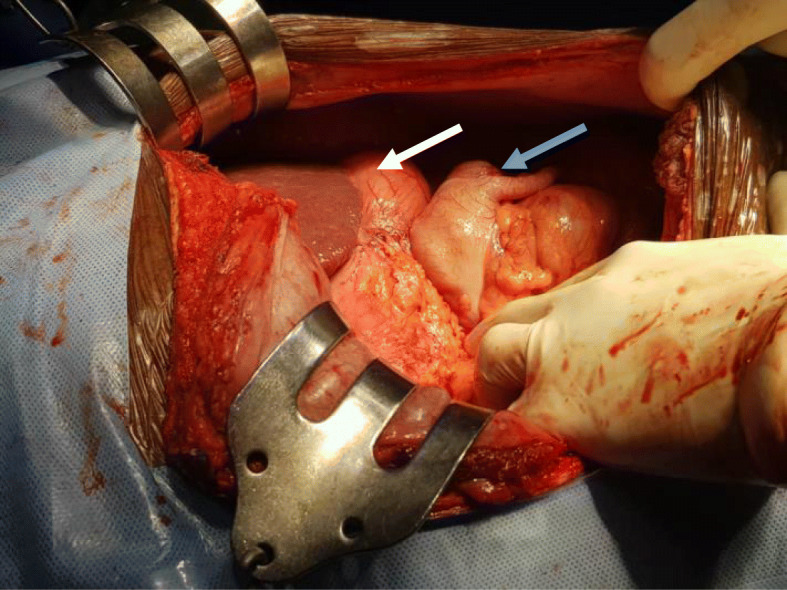

Fig. 5.

Intraoperative picture showing the cecum and appendix on the left hypochondrium (blue arrow) just below the stomach (white arrow)

Fig. 6.

Intraoperative picture showing the cecum and appendix (arrow) on the left hypochondrium